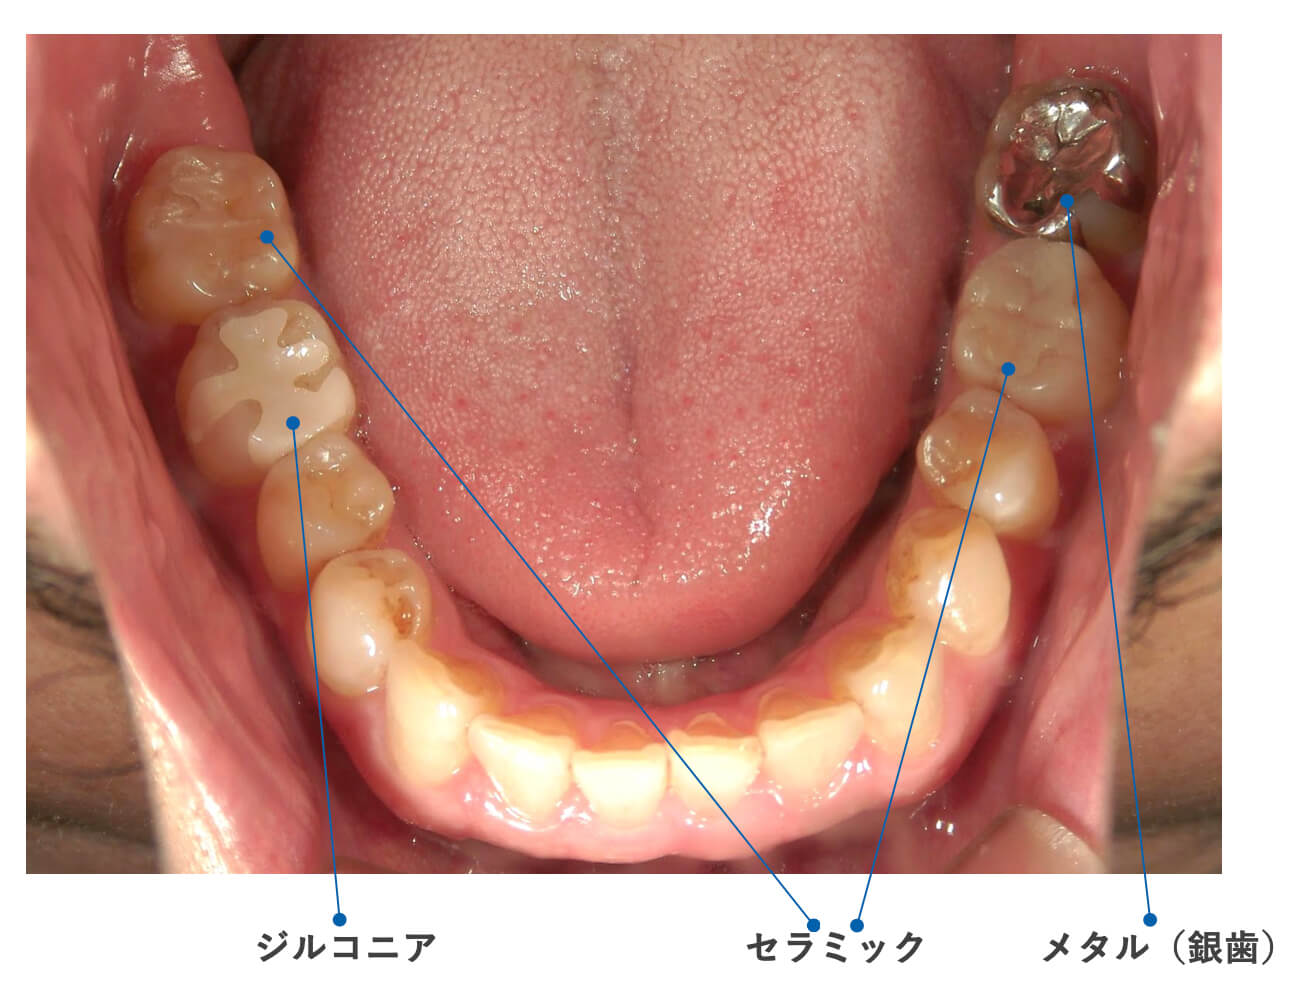

実際にお口の中を見てみましょう

素材選びの重要性について

当院では、安全性と患者様の健康のため、銀歯以外の素材をご説明しています。

ジルコニア

ジルコニアは、人工のダイヤモンドで出来ています。セラミックと比べて価格がお求めやすく、強度も勝り、とても割れにくいのが特徴です。

しかし、光を透過しないので、セラミックほどの透明感はありません。

セラミック

セラミックは、長く使われて来た歴史と安全性があります。色も透明感がありとてもキレイです。